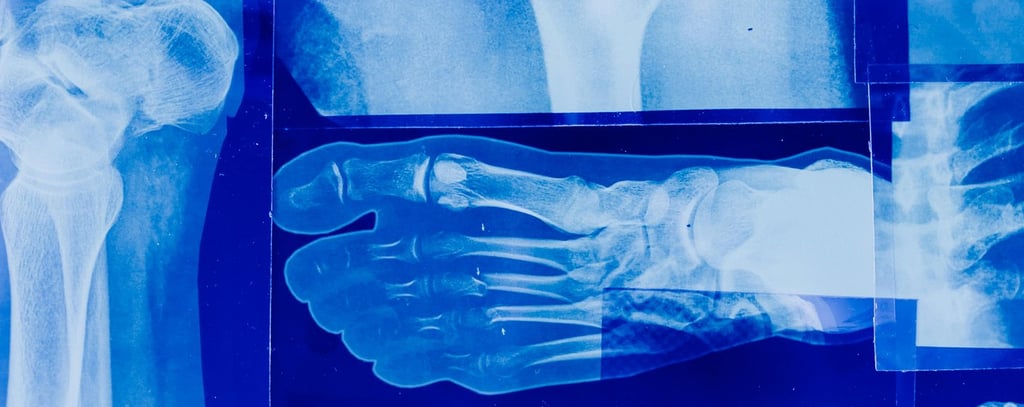

Durante la menopausia, la disminución de estrógenos acelera la pérdida de masa ósea, aumentando el riesgo de osteoporosis y fracturas. La alimentación juega un papel crucial en esta etapa, no solo para frenar esa pérdida, sino también para mantener huesos fuertes y funcionales a largo plazo.

Disminuye el riesgo de fracturas.